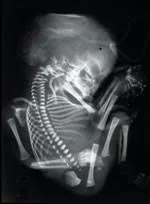

Plain Film

- Dead fetus

- Distortion of vertebral column

- Superposition of skull bones